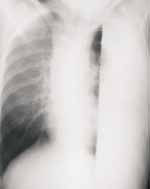

Las consolidaciones multilobares también pueden ocurrir (Figura 8), sin embargo, la consolidación total de un pulmón es rara y la opacificación total de un hemitorax es más usualmente secundaria a empiema.

FIGURA 8. Paciente lactante de sexo femenino con neumonía por neumococo, observe el componente

multilobar con compromiso casi de la totalidad del hemitórax derecho.